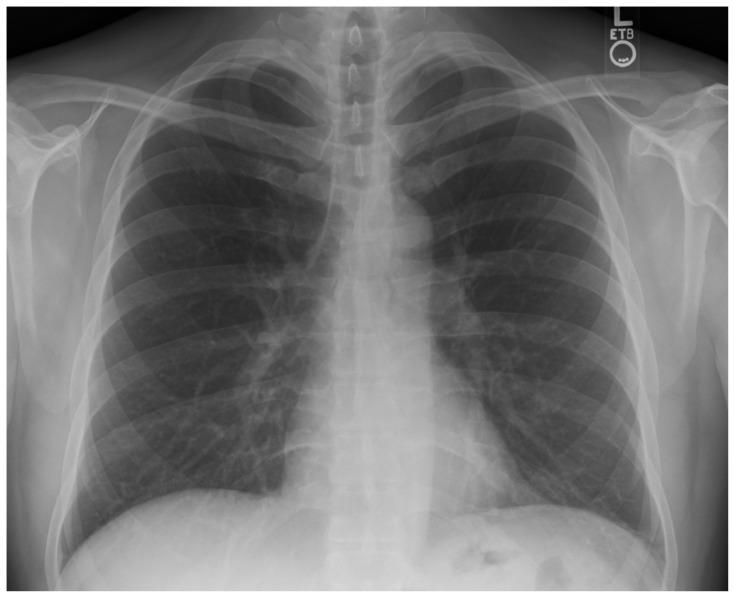

Beta-blocker (BB) toxicity ranks seventh among the top 25 substances associated with fatalities, with a cardiovascular mortality rate of up to 1.4%.1,2 Patients with BB overdose may present with bradydysrhythmias, hypotension, hypoglycemia, altered mental status, and cardiogenic shock.3 Given that EM physicians are often the first to encounter such patients, EM learners need to be proficient in managing all aspects of BB toxicity.

β受体阻滞剂(BB)中毒在导致死亡的25种物质中排名第七,心血管死亡率高达1.4%。1,2 BB过量的患者可能出现缓慢性心律失常、低血压、低血糖、精神状态改变和心源性休克。3鉴于急诊医生常常是首批接触此类患者的人,急诊医学学习者需要熟练掌握BB中毒各方面的处理。